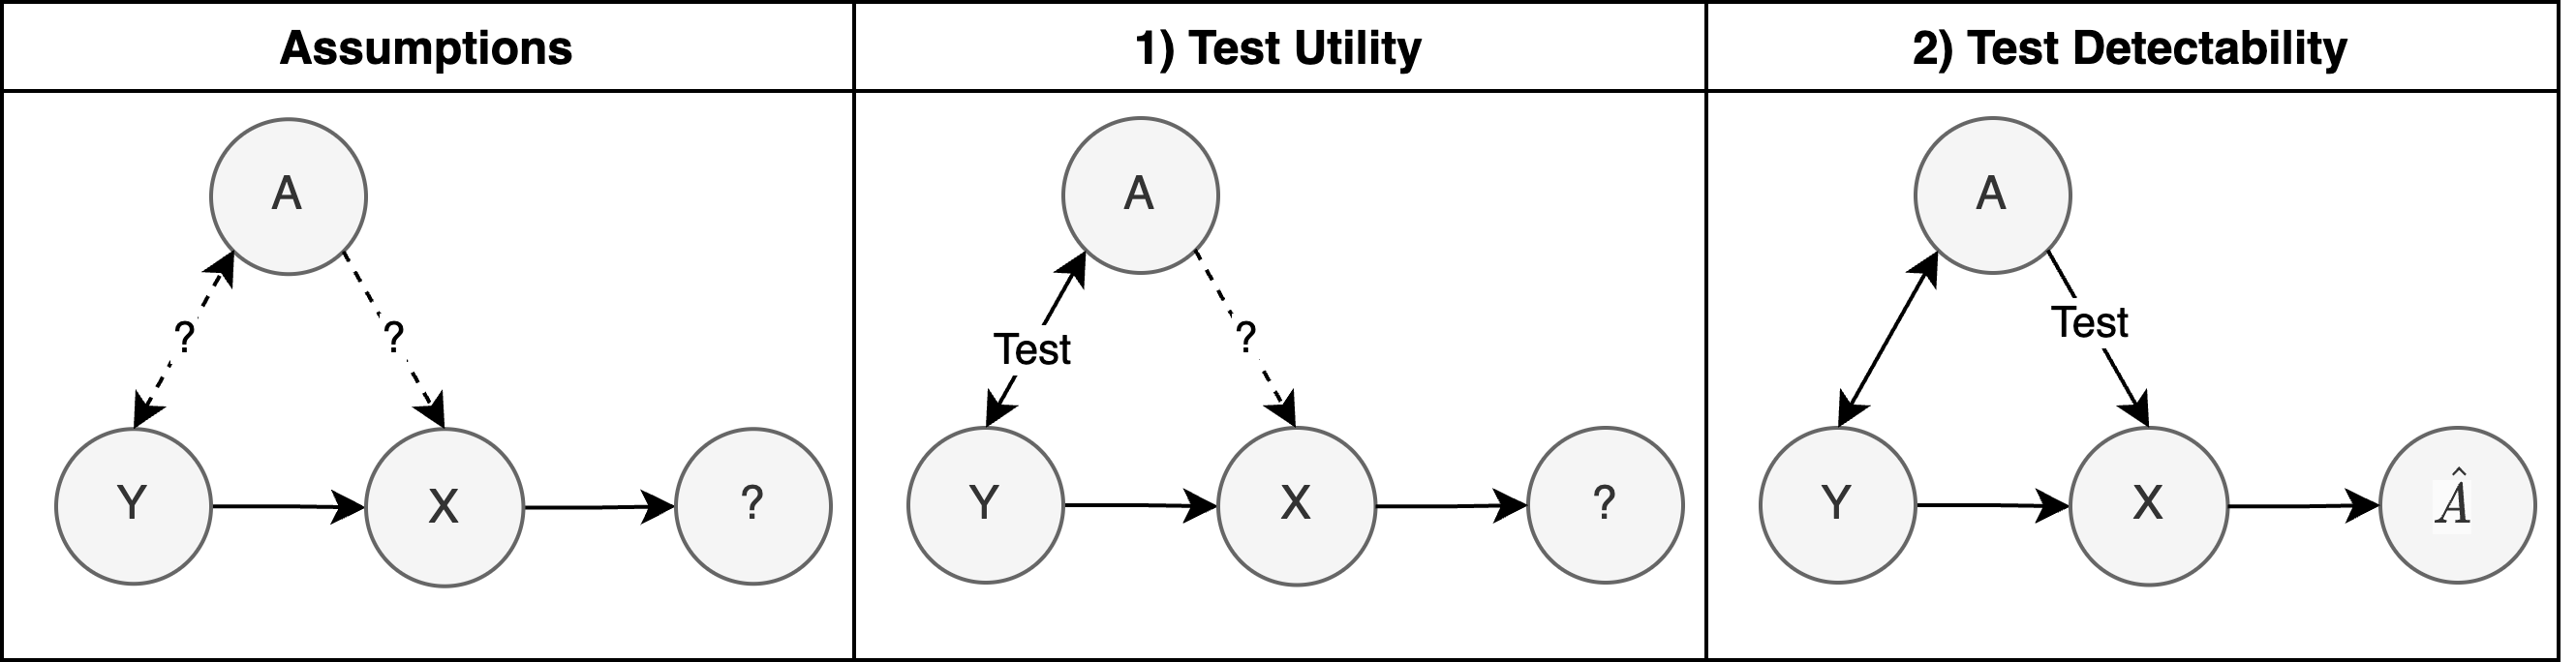

To safely deploy deep learning-based computer vision models for computer-aided detection and diagnosis, we must ensure that they are robust and reliable. Towards that goal, algorithmic auditing has received substantial attention. To guide their audit procedures, existing methods rely on heuristic approaches or high-level objectives (e.g., non-discrimination in regards to protected attributes, such as sex, gender, or race). However, algorithms may show bias with respect to various attributes beyond the more obvious ones, and integrity issues related to these more subtle attributes can have serious consequences. To enable the generation of actionable, data-driven hypotheses which identify specific dataset attributes likely to induce model bias, we contribute a first technique for the rigorous, quantitative screening of medical image datasets. Drawing from literature in the causal inference and information theory domains, our procedure decomposes the risks associated with dataset attributes in terms of their detectability and utility (defined as the amount of information knowing the attribute gives about a task label). To demonstrate the effectiveness and sensitivity of our method, we develop a variety of datasets with synthetically inserted artifacts with different degrees of association to the target label that allow evaluation of inherited model biases via comparison of performance against true counterfactual examples. Using these datasets and results from hundreds of trained models, we show our screening method reliably identifies nearly imperceptible bias-inducing artifacts. Lastly, we apply our method to the natural attributes of a popular skin-lesion dataset and demonstrate its success. Our approach provides a means to perform more systematic algorithmic audits and guide future data collection efforts in pursuit of safer and more reliable models.